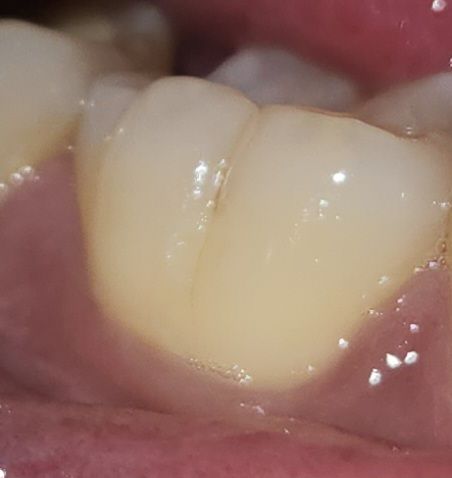

레진 2달 후 치아 시림 및 통증....무슨이유인가요

어금니(윗부분) 충치 치료후 레진을 5월 1일에 하고 이번주부터 치아 시림 및 통증이 있습니다.

세로줄은 원래 있던건지 생긴건지 모르겠는데 혹시 크랙인가요?

치료는 어떻게 해야하나요??

• 1번 째 사진

현재 사진으로는 크렉은 판단하기 어렵습니다. 다만 말씀하시는 세로줄은 원래 치아마다 존재하는 선입니다. 현재 사진으로는 상당히 애매해보이며 정확한 검사를 위해서는 치과를 방문해보아야 할 것으로 보입니다. 해당 문제가 아닌 다른 문제일 가능성이 있습니다. 가까운 시일 내에 치과 방문을 권해드립니다.

치아가 예민해져서 그럴수 있으니 일단 그쪽으로 딱딱하거나 질긴음식은 피해주시고, 사진에 보이는 세로줄은 치아에 원래 잇는 거니 걱정하지 않으셔도 됩니다.

크랙라인으로 보이는 것 같습니다. 신경치료와 크라운치료 가능성이 있으며 검사받으러 가보시는것이 좋겠습니다.